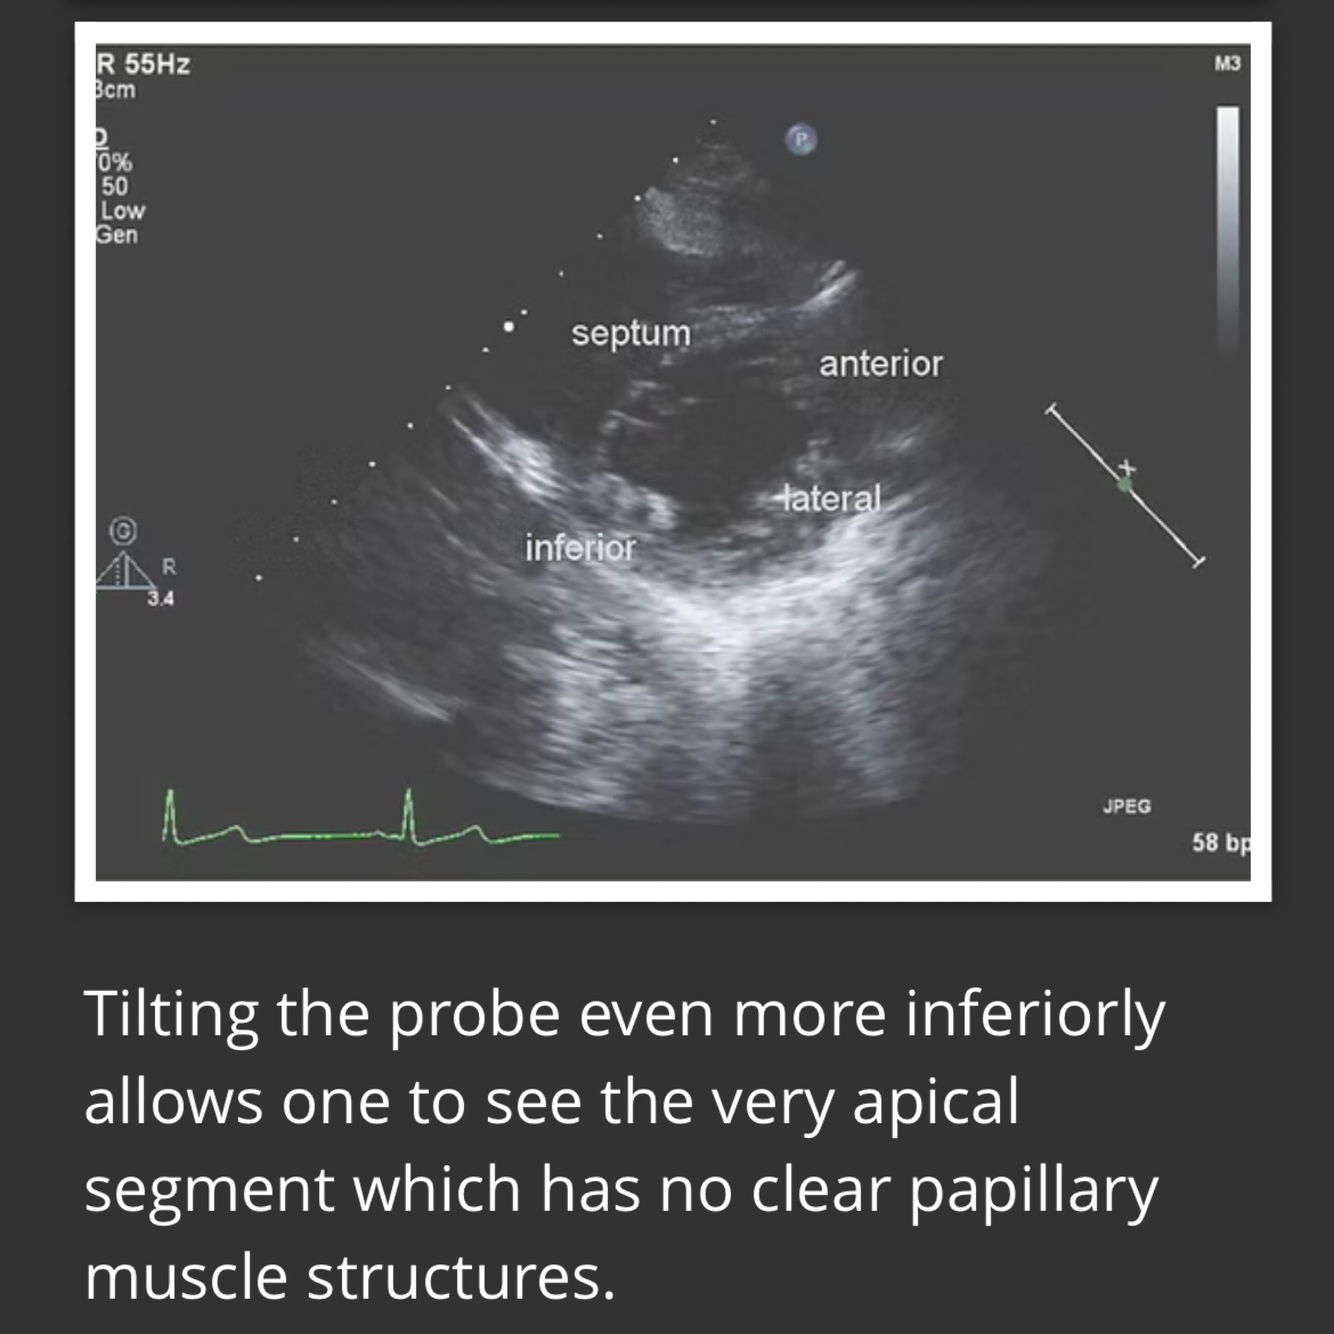

Simpsons BIPLANE method

4 chamber view

-systole and diastole

-do not include papillary or trabeculations

2 chamber view

LV biplane measurement

Straight line at MV level-height from midpoint Do NOT include papillary muscles or trabelculations No forshortening LV length perpendicular to base